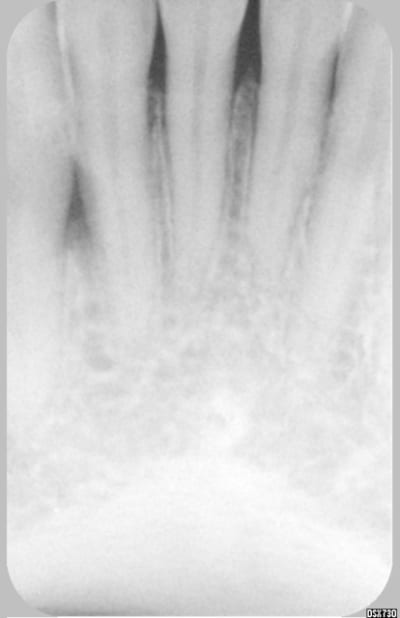

Merci pour vos réponses...voici une deuxième radio du même cas...

il me semble que cette image est typique d'une fêlure. il faut combler le sinus mandibulaire.(demandez à amibien)

ce n'est pas un vrai problème paro car le septum n'est pas touché au collet . les félures donnent il me semble une image différente.

c dingue, on dirait vraiment une lésion d'origine endo.....mais le test au froid est positif.....ceci dit le test au froid est il fiable à 100% ?? je ne crois pas.....il faudrait confirmer la vitalité pulpaire par un test électrique, voir un test du fraisage....

Une idée bête : 33 faussement réactive au test au froid, en fait nécrosée ou pulpe partiellement nécrosée (je n'ai connu cela que sur les pluriradiculées mais bon) avec lésion apicale (mouais) remontant en mésial ?

33 biradiculée (j'ai l'impression de voir quelque chose superposé à la racine, mais ce doit être la fatigue) avec 1 canal nécrosé ?

Omega a peut etre vu juste s'il y a 2 canaux, c'est vrai que la radio donne cette impression,mais la regression spontanée?